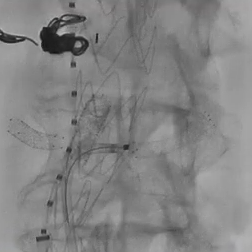

最后进行内脏动脉部分主动脉造影。注意在肾下有足够的空间(约5cm)以植入后续支架。使用普通EVAR支架完成后续的工作。

最后的正/侧位造影显示瘤腔隔绝满意,支架形态良好,主髂动脉及内脏分支动脉血流通畅。术中内脏动脉的总缺血时间<60min,肠系膜上动脉通畅在10-15min以内。

术后即刻造影